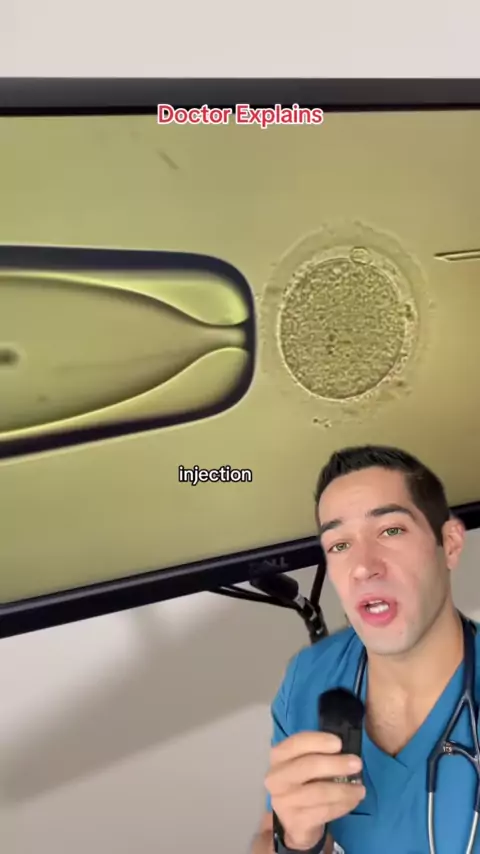

Agradeça a sua mãe, ela passou por muita coisa por você! # gravidez # fisiologia # bebê # feto # nascimento # gravidezjornada # gravidity # grávida # ėviral